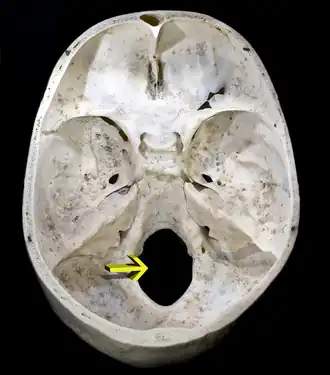

![]() Upper surface of the base of skull; the hole indicated by an arrow is the foramen magnum. | |

The foramen magnum (Latin for 'great hole') is a large, oval-shaped opening in the occipital bone of the skull. It is one of the several oval or circular openings (foramina) in the base of the skull. The spinal cord, an extension of the medulla oblongata, passes through the foramen magnum as it exits the cranial cavity. Apart from the transmission of the medulla oblongata and its membranes, the foramen magnum transmits the vertebral arteries, the anterior and posterior spinal arteries, the tectorial membranes and alar ligaments. It also transmits the accessory nerve into the skull.

The foramen magnum is a large, oval-shaped opening (foramen) in the occipital bone of the skull.[2] It is present in humans, and in many other animals. Anteriorly, it is bounded by the basiocciput.[2] Posteriorly, it is bounded by the supraocciput.[2] Laterally, it is bounded by the occipital condyles.[2]